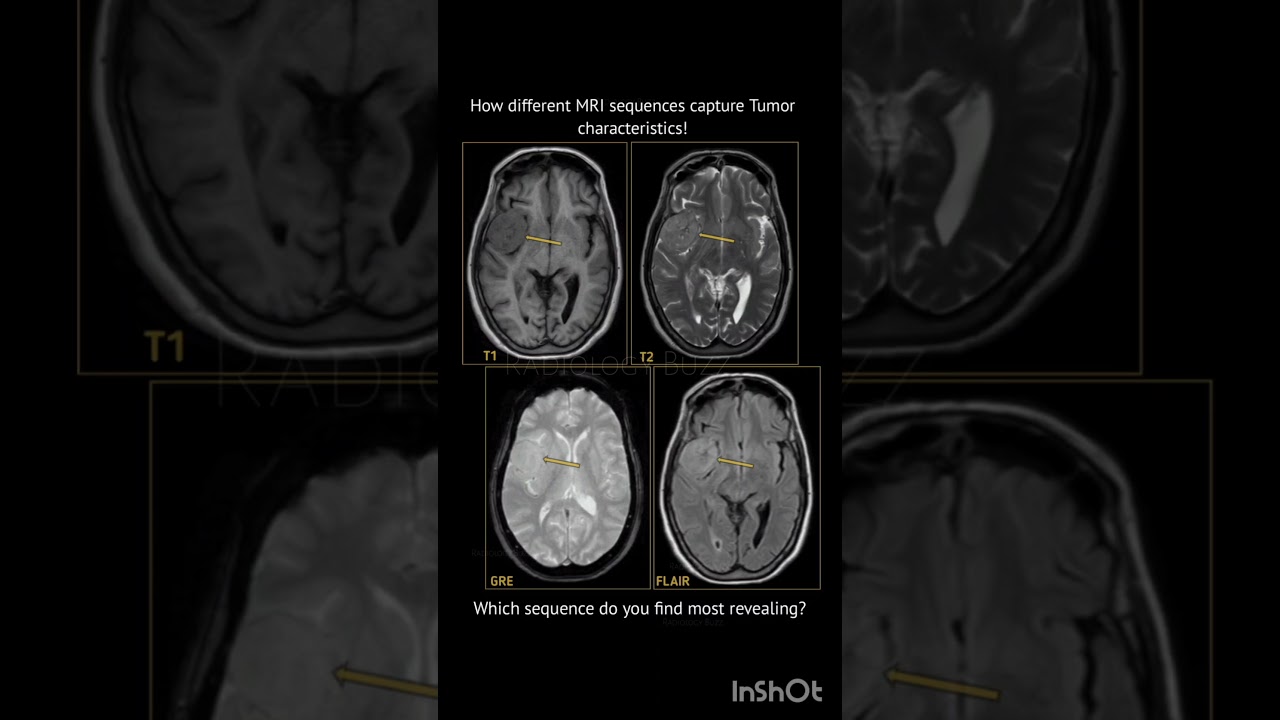

How Different Mri Sequences Highlight Tumor Characteristics

Pdf Different Types Of Mri Sequences Multiparametric mri (mpmri) combines multiple mri sequences each of which captures a unique characteristic of the tme and can, therefore, provide a more detailed insight into a tumour. Different mri sequences, such as t1 weighted and t2 weighted images, highlight distinct tissue characteristics. t1 weighted images are good for anatomical detail, while t2 weighted images are sensitive to water content and inflammation, making tumors appear brighter.

Mri Interpretation Specialised Mri Sequences Radiologists use different imaging settings, called sequences, to highlight specific tissue properties. on t1 weighted images, water rich tissues, such as many tumors, appear dark (low signal intensity). In this study, we identified radiomics that could discriminate different regions of dmg tumors (emnt, viable tumor, and peritumoral edema) in mri derived t1 and t2 sequences. Visualize brain tumor types, stages, and classification with our comprehensive guide to brain mri images, powered by cutting edge ai and deep learning. First and foremost, it offers the ability to image tissues using multiple sequences, each of which can highlight different tissue characteristics, dramatically improving diagnostic ability.